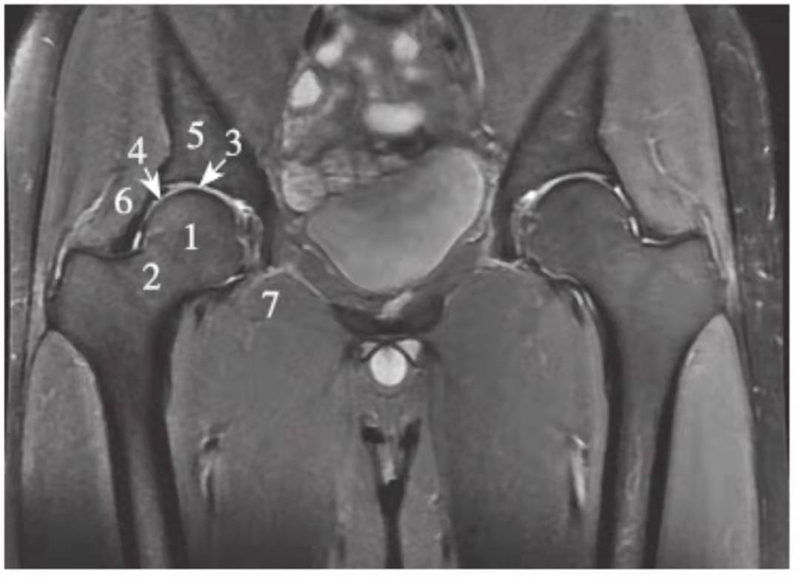

正常髋关节经股骨头中心层面PDWI抑脂像

1.股骨头;2.股骨颈;3.关节软骨;4.髋臼盂唇;5.髂骨;6.臀小肌;7.闭孔外肌